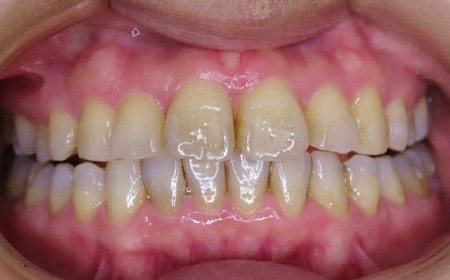

CASE01

Before

After